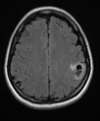

40 anos, Convulsão SWI

Oligodendroglioma Envolve córtex e substância branca Calcificação em 70 - 90% dos casos. Realce discreto ou ausente.